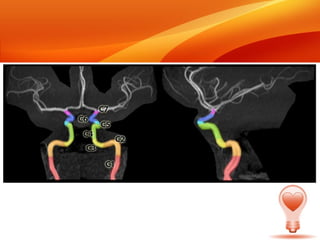

ARTERIA CAROTIDA INTERNA • La arteria se divide en cuatro partes: "cervical", "petrosa", "cavernosa" y "cerebral". No obstante, un sistema de clasificación de la carótida interna más reciente, propuesto por Bouthillier, describe siete segmentos anatómicos, este segundo sistema, de nomenclatura clínica, se basa en la apariencia angiográfica de la arteria y su relación con la anatomía circundante.

• 36.

Los segmentos dela arteria carótida interna son los siguientes: Segmento cervical, o C1, idéntico a la comúnmente conocida como porción cervical. Segmento petroso, o C2. Segmento lacerum, o C3. C2 y C3 comprenden la comúnmente conocida como porción petrosa. Segmento cavernoso, o C4, casi idéntico a la comúnmente conocida como porción cavernosa.

• 37.

Segmento clinoideo, oC5. Este segmento no está identificado en algunas clasificaciones más antiguas, y se encuentra entre las comúnmente conocidas como porción cavernosa y porción cerebral o supraclinoidea. Segmento oftálmico, o supraclinoideo, o C6. Segmento comunicante, o terminal, o C7. C6 y C7 juntos comprenden la comúnmente conocida como porción cerebral o supraclinoidea.